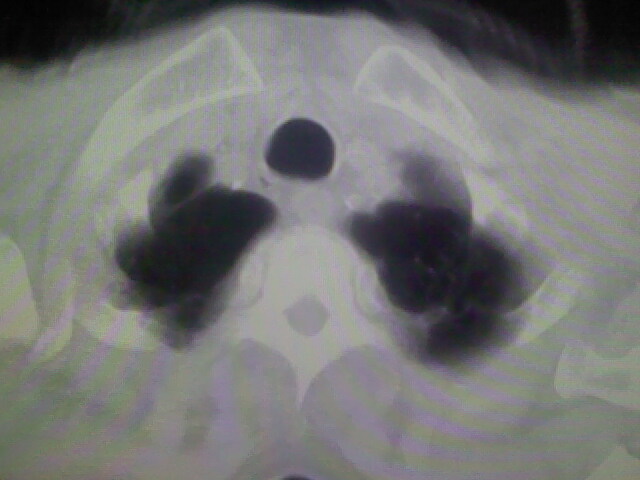

肺内考虑原发(周围型肺癌)

右上肺周围型肺癌,肝内多发低密度影---转移瘤.

1)考虑右肺上叶周围型肺癌并纵隔及右颈部淋巴结转移,肝脏多发性转移。2)肺气肿。3)冠状动脉及主动脉钙化。

1、右肺上叶周围型肺癌并纵隔、颈部淋巴结转移,肝多发转移灶。

右上肺周围型肺癌;肝内多发转移瘤?建议增强;